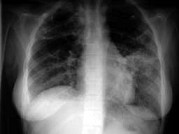

- 单项选择题女,18岁, 1年前患肺结核经抗结核治疗后好转,现发热、咳嗽、体重下降, 结合CT图像,最可能的诊断是 ( )

A、肺结核

B、肺炎

C、肺脓肿

D、肺转移瘤

E、细支气管肺泡癌